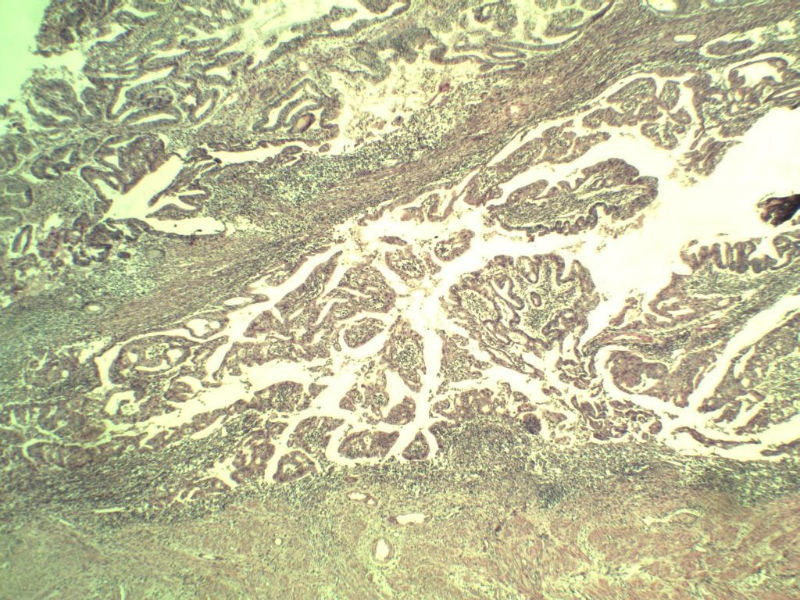

女,57岁,全切子宫一个,宫体体积 9 × 8 × 7 cm3,肌壁厚 2.5 cm,内膜菲薄,部分区域增厚达 0.4 cm(约3*2.5cm区域)。 请问各位老师  这个可以诊断子宫内膜癌了吧?      深肌层没有看到浸润。

患者因"发现下腹部包块1月多"入院  宫体体积 9 × 8 × 7 cm3,肌壁厚 2.5 cm,内膜菲薄,部分区域厚 0.4 cm(约3*2.5cm)。宫颈结构不清,长约 2.5 cm,表面欠光滑。临床诊断宫颈宫腔积液.

宫内膜样腺癌

筛状、迷路样结构

间质消失或者纤维性间质

子宫内膜样腺癌

高分化子宫内膜样癌。浸润浅肌层(深度<1/3肌层)。根据FIGO2009分期,子宫内膜癌局限于内膜层和<1/2肌层,都属于IA期。二者处理不再区别对待。